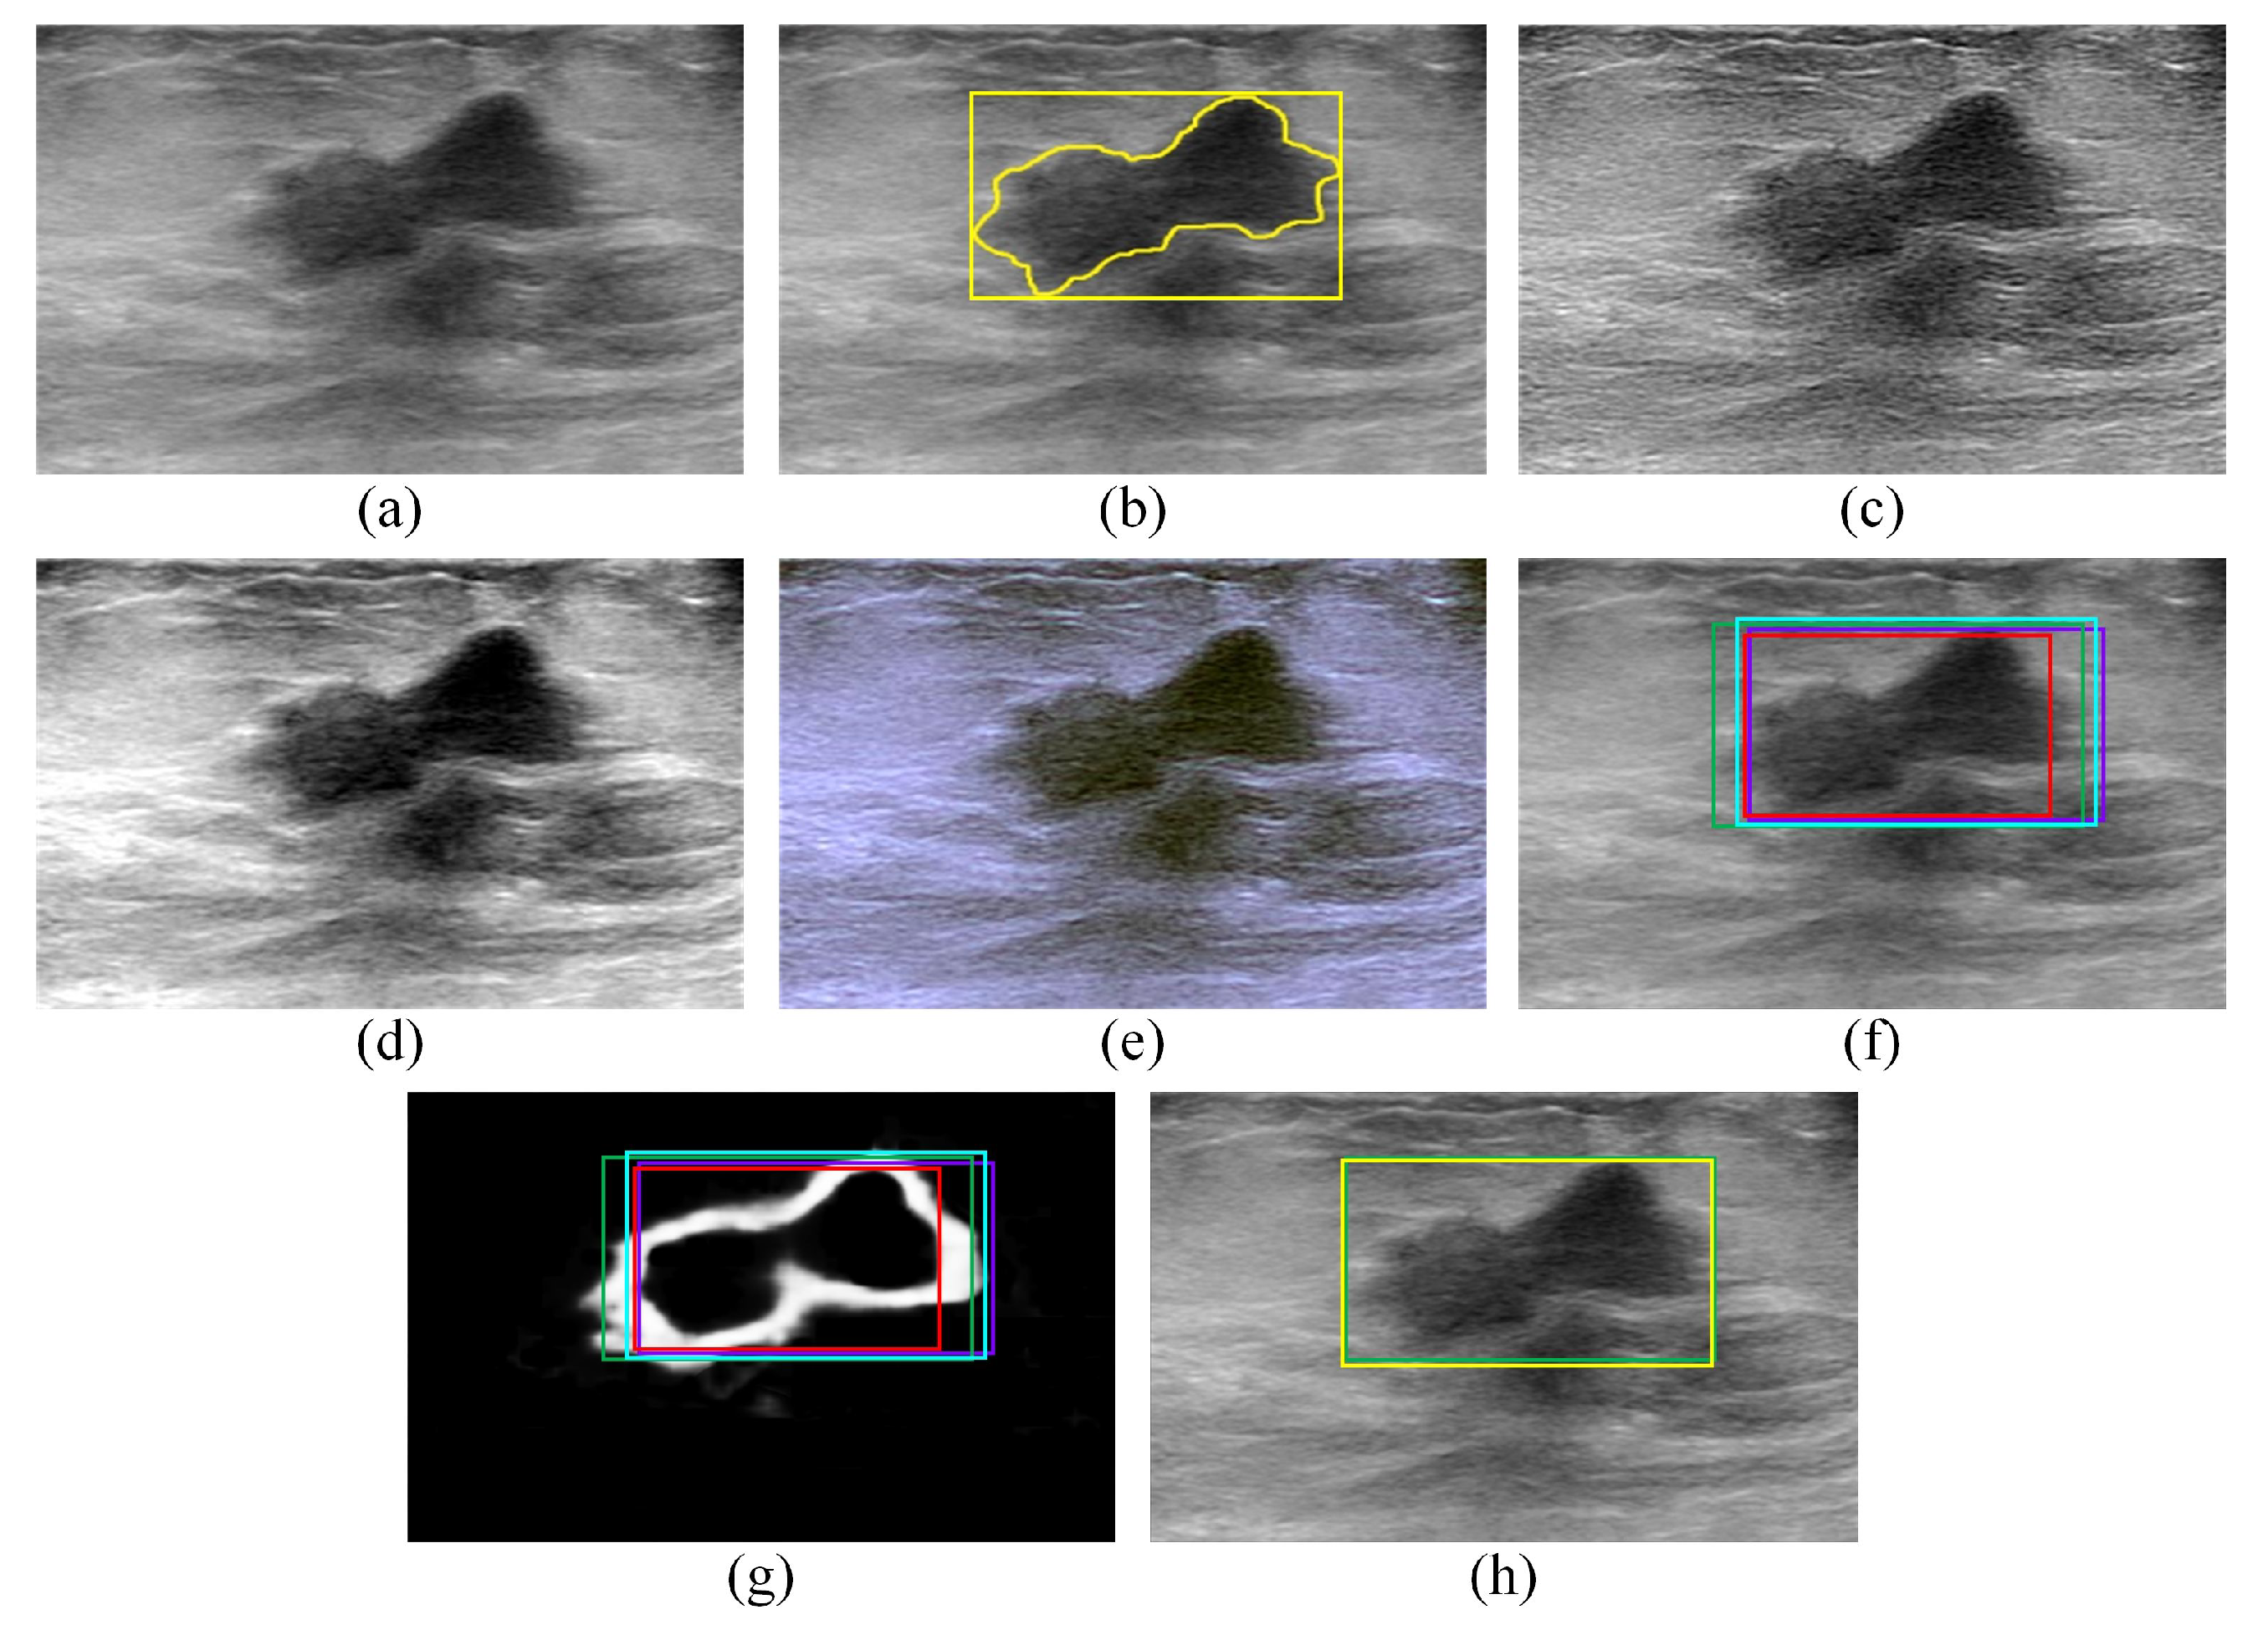

2.2.1. Transforming the BUS Images into Artificial RGB Images

2.2.2. Employing the Faster R-CNN Model to Localize ROIs That Contain the Tumors

2.2.3. Employing the SSD Model to Localize the ROIs That Contain the Tumors

2.2.4. Employing the EfficientDet-D0 Model to Localize ROIs That Contain Tumors

2.2.5. Employing the CenterNet Model to Localize ROIs That Contain Tumors

2.2.6. Employing the Proposed Edge-Based Selection Method to Select ROIs That Enable the Effective Detection of Regions That Contain Tumors